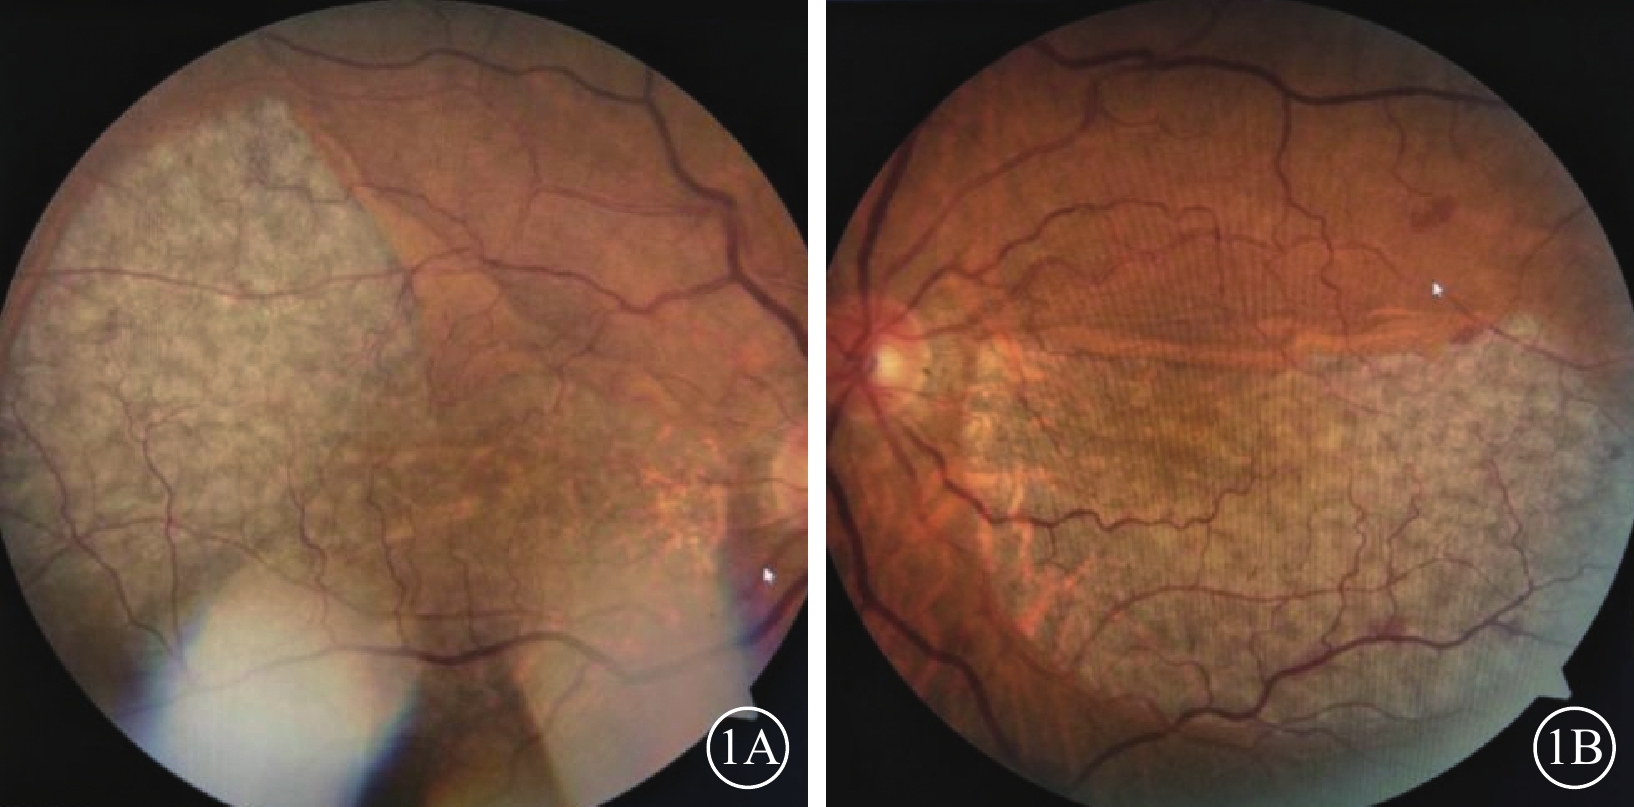

患者女,68歲。因雙眼視物模糊20 d于2018年3月20日來我院眼科就診。既往肺心病10年;否認雙眼外傷史,否認遺傳病家族史。眼部檢查:雙眼視力0.1,均不能矯正。右眼眼壓16 mmHg(1 mmHg=0.133 kPa),左眼眼壓15 mmHg。雙眼眼前節檢查正常。眼底檢查,雙眼后極部巨大RPE撕裂,撕裂區透見脈絡膜水腫;上方RPE收縮卷曲皺褶;視網膜血管紆曲(圖1)。OCT檢查,后極部撕裂區RPE信號消失。對應RPE卷曲皺褶處強反射隆起信號。未撕裂范圍RPE信號正常(圖2)。因患者原因未行FFA檢查。臨床診斷:雙眼特發性RPE撕裂。

圖1

雙眼彩色眼底像。1A示右眼,后極部巨大不規則形RPE撕裂,上方可見皺褶隆起。隆起處視網膜血管呈爬坡樣;1B示左眼,后極部半月形撕裂區,上方RPE收縮卷曲,視網膜小靜脈有毛刷樣出血

圖1

雙眼彩色眼底像。1A示右眼,后極部巨大不規則形RPE撕裂,上方可見皺褶隆起。隆起處視網膜血管呈爬坡樣;1B示左眼,后極部半月形撕裂區,上方RPE收縮卷曲,視網膜小靜脈有毛刷樣出血

患者女,68歲。因雙眼視物模糊20 d于2018年3月20日來我院眼科就診。既往肺心病10年;否認雙眼外傷史,否認遺傳病家族史。眼部檢查:雙眼視力0.1,均不能矯正。右眼眼壓16 mmHg(1 mmHg=0.133 kPa),左眼眼壓15 mmHg。雙眼眼前節檢查正常。眼底檢查,雙眼后極部巨大RPE撕裂,撕裂區透見脈絡膜水腫;上方RPE收縮卷曲皺褶;視網膜血管紆曲(圖1)。OCT檢查,后極部撕裂區RPE信號消失。對應RPE卷曲皺褶處強反射隆起信號。未撕裂范圍RPE信號正常(圖2)。因患者原因未行FFA檢查。臨床診斷:雙眼特發性RPE撕裂。

圖1

雙眼彩色眼底像。1A示右眼,后極部巨大不規則形RPE撕裂,上方可見皺褶隆起。隆起處視網膜血管呈爬坡樣;1B示左眼,后極部半月形撕裂區,上方RPE收縮卷曲,視網膜小靜脈有毛刷樣出血

圖1

雙眼彩色眼底像。1A示右眼,后極部巨大不規則形RPE撕裂,上方可見皺褶隆起。隆起處視網膜血管呈爬坡樣;1B示左眼,后極部半月形撕裂區,上方RPE收縮卷曲,視網膜小靜脈有毛刷樣出血